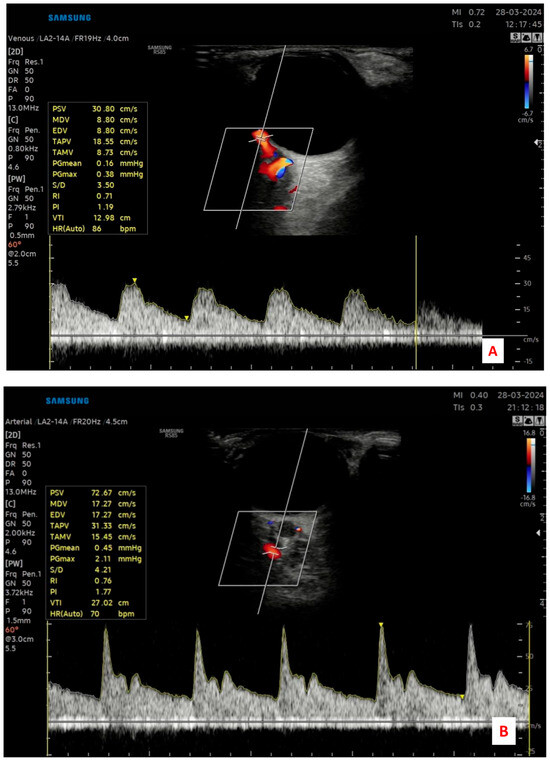

Measurements were taken from the ophthalmic artery (OA), central retinal artery (CRA), and posterior ciliary artery (PCA). For each vessel, the pulsatility index (PI) and resistive index (RI) were automatically calculated by the device’s built-in software, using waveform analysis. Care was taken to maintain the angle of insonation at ≤60° to optimize Doppler signal accuracy and avoid angular artifacts. The sample volume was adjusted to the vessel size, and the gate was placed in the center of the vessel lumen during measurement. Each measurement was obtained when a clear and stable Doppler waveform was visible, and three consecutive cardiac cycles were recorded for consistency (Figure 1).

Figure 1.

Representative color Doppler ultrasonography images demonstrating the retrobulbar blood flow assessment in a study participant. (A) Central retinal artery (CRA) identified within the optic nerve sheath; (B) Ophthalmic artery (OA) measured at the orbital apex; and (C) Posterior ciliary artery (PCA) evaluated near the optic nerve entry site.